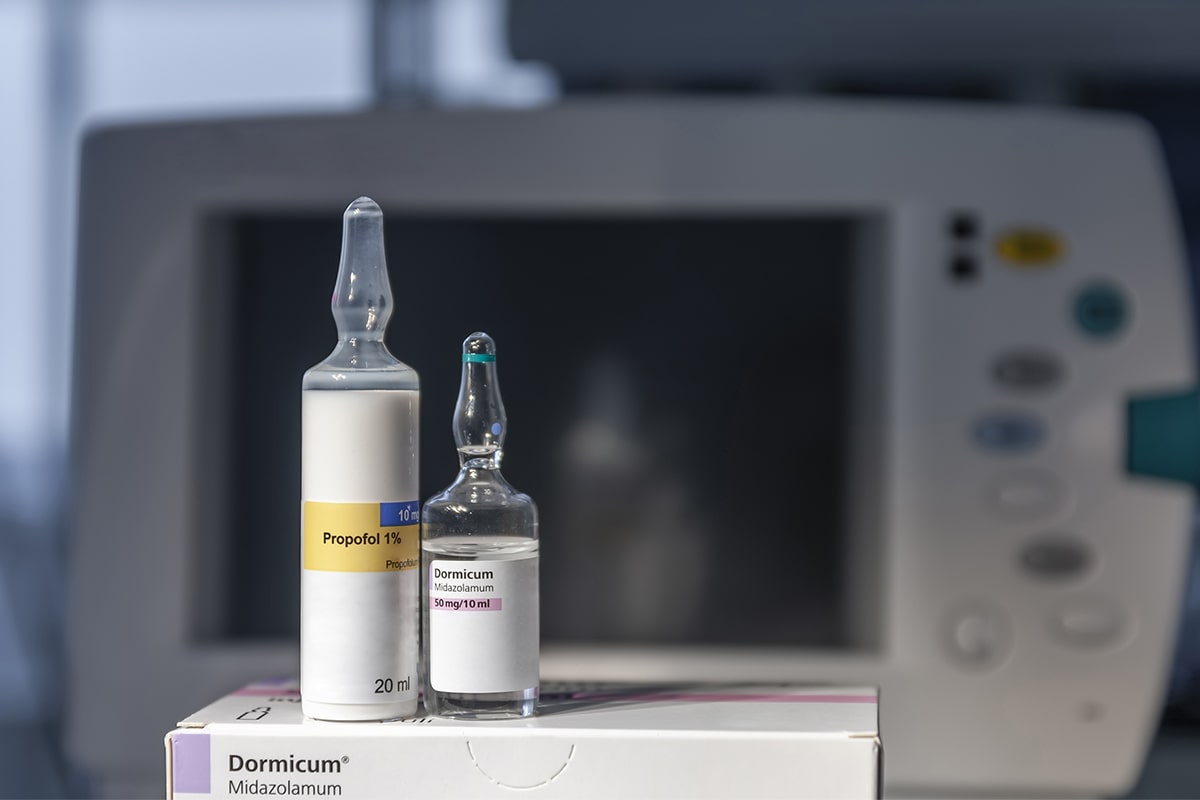

Éber szedálás

- korábbi traumából, félelemből eredő félős pácienseknek javasolt kezelési mód

- hosszabb kezeléseket is rövidebb időnek éli meg a páciens

- mámoros, nyugodt állapotot biztosítunk ezzel

- aneszteziológus szakorvos végzi a kezelést